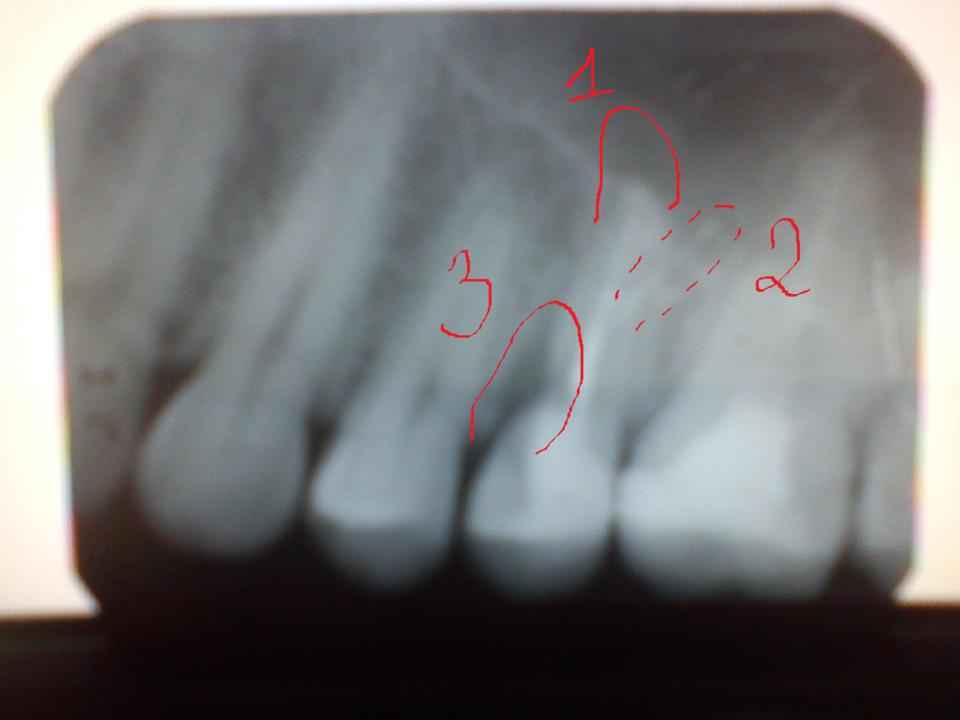

paraschyk1 Опубліковано: 28 лютого 2015 Автор Опубліковано: 28 лютого 2015 Смотри,профи эндодонт с микроскопом сможет распломбировать почти любой канал,вытащить с канала обломок или обойдет его.,или вкладку металлическую или штифт. Но есть случаи когда и после этого воспалительный процесс не проходит,тогда есть работа для хирурга и он делает резекцию корня зуба(апикальная хирургия).Но здесь тоже нужен толковый врач.Успешная апикальная хирургия это последовательность: хорошо перелеченный канал,резекция корня,апикальная пломба резекцированого корня. Тогда будет гут. Очень окуиьельно если апикальную хирургию делает сам эндодонт микроскопист. А в члх тебе просто выскоблят кисту или гранулему и заштопают.А инфекция то откуда-то там взялась до этого.Потом рецедив через несколько лет. Вижу три предполагаемые проблемы. Первое,имхо,процесс за верхушкой корня (инфекшн),второе-перфорация (дырка) корня и в ней материал,третий- карман,возможно,с внешней резобцией (на пальцАх розссасывание) корня. Нужно КТ зоны. Если будет подтверждения хотя бы двух из трех,я бы не брался за такой зуб,ну или ты был моей тещей. Если нет,то перелечивание каналов с закрытием перфорации,восстановление зуба на стекловолокне,обточка временная и коронка с хорошими контактами. Через пол года повторное КТ,сравнение,анализ выбор дальнейшего пути. Если 2 из трех-удаление,перелечивание каналов в шестом зубе,а далее по финансам или шуруп,или адгезивный мост. Но я врач маленький могу иметь ошибочное мнение.

Flex27 Опубліковано: 1 березня 2015 Опубліковано: 1 березня 2015 Вижу три предполагаемые проблемы. Первое,имхо,процесс за верхушкой корня (инфекшн),второе-перфорация (дырка) корня и в ней материал,третий- карман,возможно,с внешней резобцией (на пальцАх розссасывание) корня. Нужно КТ зоны. Если будет подтверждения хотя бы двух из трех,я бы не брался за такой зуб,ну или ты был моей тещей. Если нет,то перелечивание каналов с закрытием перфорации,восстановление зуба на стекловолокне,обточка временная и коронка с хорошими контактами. Через пол года повторное КТ,сравнение,анализ выбор дальнейшего пути. Если 2 из трех-удаление,перелечивание каналов в шестом зубе,а далее по финансам или шуруп,или адгезивный мост. Но я врач маленький могу иметь ошибочное мнение. а зачем адгезивный мост? Депульпированый шестой с огромной пломбой, четвертый с плохим апроксимальным контактом и пломбой. При удалении пятого все показания для мостовидного протеза,штамповано-паяного....шютка. мое имхо-5 зуб г..но. баловаться можно,но выченки не стоит.. кучу бобла ввалите,а гарантии никто не даст.. Скока качей стоматоидов...я лично знаю 3..и тут еше банда.

paraschyk1 Опубліковано: 1 березня 2015 Автор Опубліковано: 1 березня 2015 а зачем адгезивный мост? Депульпированый шестой с огромной пломбой, четвертый с плохим апроксимальным контактом и пломбой. При удалении пятого все показания для мостовидного протеза,штамповано-паяного....шютка. мое имхо-5 зуб г..но. баловаться можно,но выченки не стоит.. кучу бобла ввалите,а гарантии никто не даст.. Скока качей стоматоидов...я лично знаю 3..и тут еше банда. Имхо в 4ке нет пломбы,просто такая проекция с наложением эмали. Как максимум,если без импл,то не классический мост мк,а на прессе